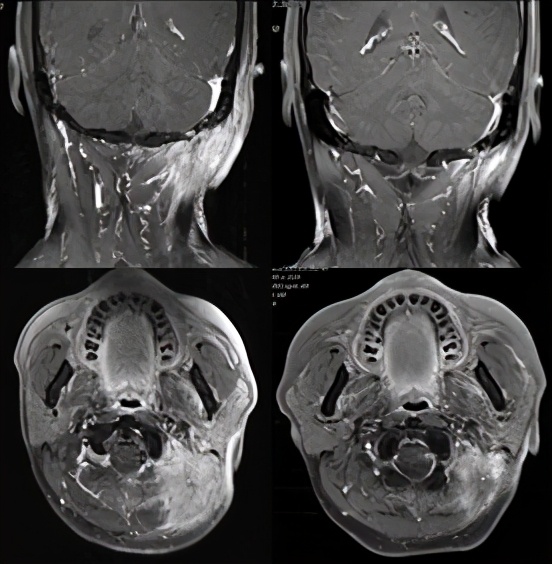

德瓦鲁单抗联合放疗后第一次评价(左:2020.5.11;右:治疗后2020.9)

3.PD-L1单抗药物可逆转部分PD-1单抗耐药的患者。Clinical Lung Cancer曾发表了一例PD-1单抗耐药后尝试PD-L1单抗有效的治疗案例。79岁的女性患者于2014年7月被诊断为局部晚期鳞状非小细胞肺癌,一线接受序贯放化疗,二线治疗使用PD-1单抗O药(Nivolumab),病情进一步恶化,患者使用卡铂联合紫杉醇,但随即又开始进展。在2018年11月患者使用PD-L1单抗T药(Atezolizumab,1200mg,q3w)作为四线治疗。在第一次影像学评估时,就已经达到了部分缓解(PR),在2019年3月达到了最大影像学缓解。至今用药的9个月期间并未出现3-4级毒性,目前还在持续治疗中。本例患者PD-1信迪利单抗耐药后,患者使用德瓦鲁单抗(durvalumab)联合TP方案化疗:德瓦鲁单抗注射液620mg d1+白蛋白紫杉醇400mg d1+奈达铂50mg d2-4,q3w),第一次影像学评估时,就已经达到了部分缓解(PR),后续德瓦鲁单抗(durvalumab,620mg d1,q3w)联合局部放疗,影像评估时即达到cCR。至今用药12个月,期间没有毒副反应,目前仍在治疗中。